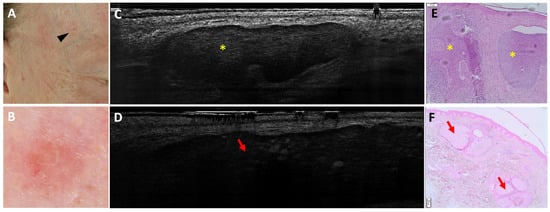

- Suppa, M.; Fontaine, M.; Dejonckheere, G.; Cinotti, E.; Yélamos, O.; Diet, G.; Tognetti, L.; Miyamoto, M.; Orte Cano, C.; Perez-Anker, J.; et al. Line-field confocal optical coherence tomography of basal cell carcinoma: A descriptive study. J. Eur. Acad. Dermatol. Venereol. 2021, 35, 1099–1110. [Google Scholar] [CrossRef]

- Ruini, C.; Schuh, S.; Gust, C.; Kendziora, B.; Frommherz, L.; French, L.E.; Hartmann, D.; Welzel, J.; Sattler, E. Line-field optical coherence tomography: In vivo diagnosis of basal cell carcinoma subtypes compared with histopathology. Clin. Exp. Dermatol. 2021, 46, 1471–1481. [Google Scholar] [CrossRef]

- Boussingault, L.; Lenoir, C.; Stefani, A.D.; Cappilli, S.; Fontaine, M.; Diet, G.; Miyamoto, M.; Cinotti, E.; Tognetti, L.; Pérez-Anker, J.; et al. Line-Field Confocal Optical Coherence Tomography of Basal Cell Carcinoma: Systematic Correlation with Histopathology. Diagnostics 2025, 15, 3059. [Google Scholar] [CrossRef] [PubMed]

- Donelli, C.; Suppa, M.; Tognetti, L.; Perrot, J.L.; Calabrese, L.; Pérez-Anker, J.; Malvehy, J.; Rubegni, P.; Cinotti, E. Line-Field Confocal Optical Coherence Tomography for the Diagnosis of Skin Carcinomas: Real-Life Data over Three Years. Curr. Oncol. 2023, 30, 8853–8864. [Google Scholar] [CrossRef]